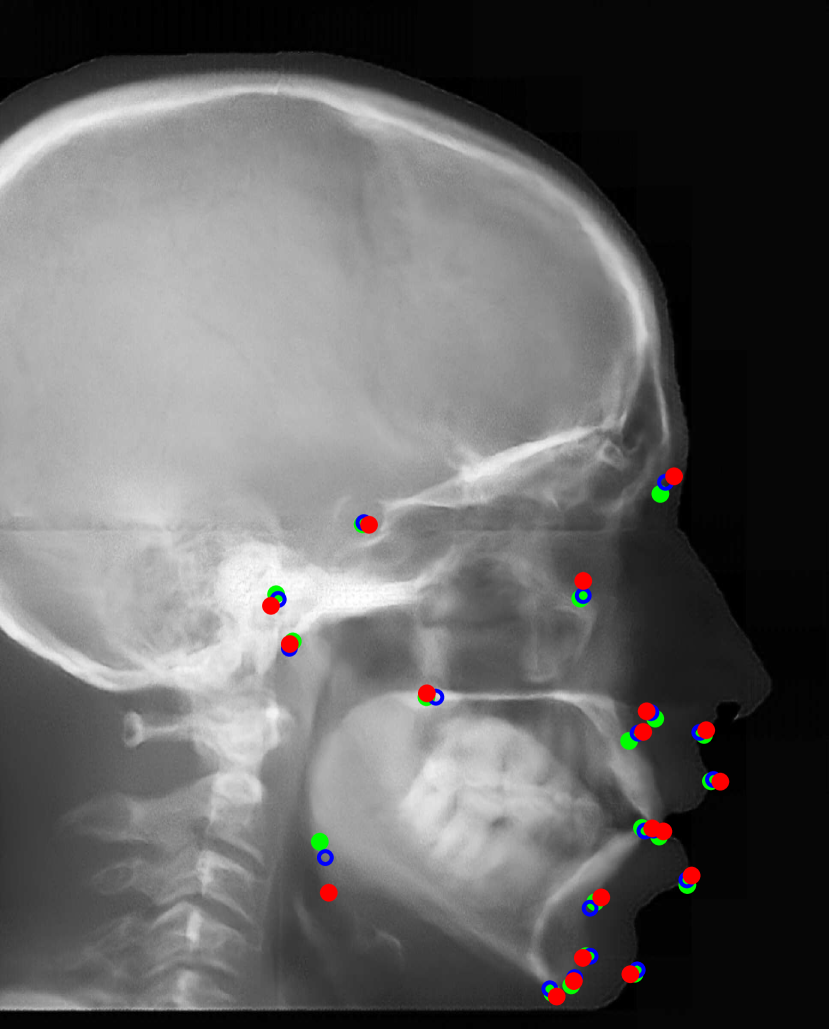

Fig. 16: Landmark detection on synthetic cephalograms. Cephalograms in the top row are obtained by different synthesis methods from 3D volumes for the first patient with pix2pixGAN for SR. The second row shows Type I synthetic cephalograms with different SR methods. The 3rd and bottom rows are Type I and Type II synthetic cephalograms respectively from three example patients with pix2pixGAN for SR. The green (reference) and blue labels are manual detection landmark positions in Type I and Type II synthetic cephalograms respectively, while the red labels are automated detection landmark positions in each cephalogram.

Our proposed landmark detection method is applied to detect landmarks in synthetic cephalograms. The results of three example patients are displayed in Fig. 16. Cephalograms in the top row are obtained by different synthesis methods from 3D volumes for the first patient with pix2pixGAN for SR. The second row shows Type I synthetic cephalograms with different SR methods. The 3rd and bottom rows are Type I and Type II synthetic cephalograms respectively from three example patients with pix2pixGAN for SR. The green and blue labels are manual detection landmark positions in Type I and Type II synthetic cephalograms respectively, while the red labels are automated detection landmark positions in each cephalogram. The green labels are used as the reference. The overall SDRs of the landmarks in different types of synthetic cephalograms on the test patients are displayed in Tab. 4. The last row SDRs are calculated from manual detection (blue) landmarks in Type II synthetic cephalograms w. r. t. reference landmarks, while others are from automatic detection (red) landmarks w. r. t. reference landmarks.

For RayCast in Fig. 16(a), many automatic detection landmarks exceed the 4 mm precision range such as the landmarks of anterior nasal spine, gonion, porion and articulare. According to Tab. 4, overall only 45.6% landmarks are detected within the 4 mm precision range by the automatic landmark detection algorithm. For MIP100 in Fig. 16(b), the landmarks of sella, porion, articulare have very large deviations from the reference landmarks. Overall, it achieves 47.4% 2 mm-SDR and 81.5% 4 mm-SDR. Figs. 16(c) and (g) are the cephalograms synthesized by our Type I synthesis with the original sigmoid transform and the modified sigmoid transform, respectively. These two synthetic cephalograms have subtle difference in the soft-tissue areas. As a result, the detected incision superius and lower lip positions exceed the 4 mm range in Fig. 16(c) while they are well detected within the 2 mm precision range in Fig. 16(g). This demonstrates the benefit of the modified sigmoid transform.

In Figs. 16(d)-(f), the landmark detection accuracies are very close to each other for the other 18 landmarks except for the sella landmark. The point-to-point errors are 9.77 mm, 4.57 mm, and 1.65 mm respectively in Figs. 16(d)-(f) for the sella. Tab. 4 indicates that overall 66.7% landmarks are detected within the 2 mm precision range for bicubic interpolation. For ESRGANRDB and ESRGANRRDB using ILR patches, the 2 mm-SDR rises to 70.2% and 71.9%, respectively. Nevertheless, pix2pixGAN achieves the best 2 mm-SDR 75.4% among different SR methods for Type I synthesis. Therefore, different SR methods have an influence on the landmark detection.

For Type I synthesis, two more cephalograms are displayed in Figs. 16(h) and (i). Overall, 93.0% automatic detection landmarks are overlapped with the reference landmarks within the precision range of 4 mm, with a few exceptions such as the sella landmark in (g), the porion in (h), and the incision inferius and subnasale landmarks in (i) beyond 4 mm. Particularly, 75.4% automatic detection landmarks are within the 2 mm clinical acceptable precision range. This indicates that the automatic landmark detection algorithms learned from real conventional cephalograms can be applied to our Type I synthetic cephalograms.

For Type II synthetic cephalograms in Figs. 16(j)-(l), all the manual detection (blue) landmarks are overlapped with the reference landmarks within the distance range of 4 mm, indicating that the landmark positions in the Type II synthetic cephalograms have no impactful position shift from those in Type I synthetic cephalograms. The majority (80.7%) of the automatic detection (red) landmarks are also overlapped with the reference landmarks within the 4 mm precision range. However, more automatic detection landmarks in Type II synthetic cephalograms are outside the 4 mm range than those in Type I synthetic cephalograms, for example, the anterior nasal spine landmark in (j), the orbitale landmark in (k), the incision inferius landmark in (l), the nasion landmarks in (k) and (l), and the gonion landmarks in (j)-(l). The 2 mm-SDR also decreases from 75.4% to 50.9%.